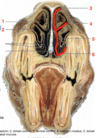

Name the structures that are shown below:

- dorsal concha

- ventral concha

- ethomoidal concha

Name the following features:

- Dorsal Concha

- Ventral concha

- Dorsal meatus

- Middle meatus

- Common meatus

- Ventral meatus